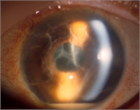

1. 感染性眼内炎とは病原微生物の眼内感染により生じる虹彩毛様体炎、網脈絡膜炎の総称である。